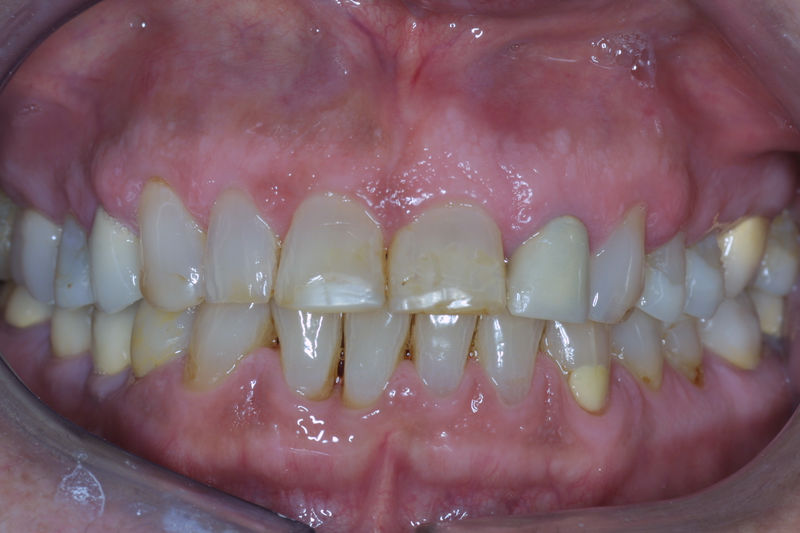

Implante fracasado, extracción, carillas, coronas y prótesis fija.

Implantes, ortodoncia y coronas.

Ortodoncia y coronas.

Cirugía ortognática, implantes, carillas y coronas,